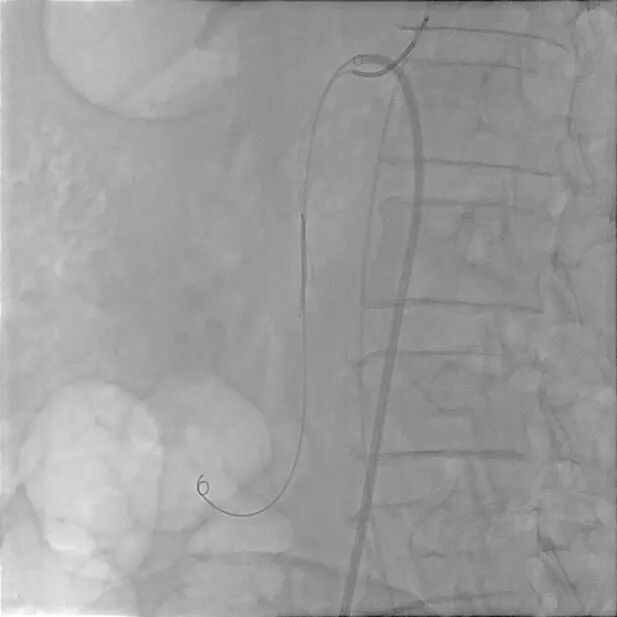

夹层动脉瘤内弹簧圈栓塞

患者取仰卧位,双侧腹股沟区消毒铺单后局麻下分别经双侧股动脉穿刺置入7F(右侧)/5F(左侧)血管鞘组,予40mg肝素钠静脉注射全身肝素化,先经左股动脉插入4FRH导管,将导管头端置于肠系膜上动脉开口处,注入对比剂行肠系膜上动脉IADSA;再经右侧股动脉插入7F长鞘至肠系膜上动脉开口,旁路加压滴注生理盐水;明确病情后选取工作角度,先经4FRH导管路途下同轴送入1.7F栓塞微导管,旁路加压滴注生理盐水,经微导丝配合将其头端至于肠系膜上动脉夹层囊状动脉瘤腔内,于动脉瘤填入5枚弹簧圈行夹层动脉瘤弹簧圈填塞术;经右侧股动脉长鞘入路沿导丝送入1枚支架(SmartFlex 6mm×80mm,USA)该支架具有可预见的近端定位+参考Marker,准确定位后行肠系膜上动脉真腔成形术,支架覆盖夹层段。复行肠系膜上动脉IADSA示:支架位于肠系膜上动脉主干夹层段,支架覆盖夹层动脉瘤出入破口,支架内血流通畅,分支血管显影良好,支架以远血管主干及分支显影较术前增多增浓,多发夹层动脉瘤腔内弹簧圈均匀填塞。手术结束,使用Exoseal封堵止血系统闭合双侧股动脉穿刺点。